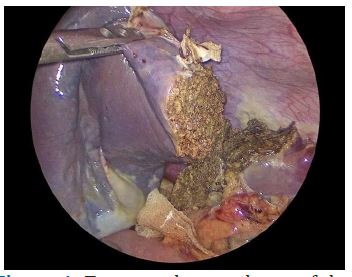

We scheduled a multidisciplinary discussion with surgeons, radiologists and paediatricians and decided to manage the cystic lesion by laparoscopic partial splenectomy with ultrasound guidance. The patient had been previously vaccinated for encapsulated bacteria and was prescribed perioperative antibiotic prophylaxis with cefazoline and anti-thromboembolic prophylaxis with enoxaparin. The operation was performed under general anaesthesia. The patient was placed in a supine position on the operative table and we placed four trocars (three 5 mm trocar and one 15 mm trocar) as described in previous works [6]. The exploration of the abdomen showed a cystic lesion of the upper pole of the spleen (Figure 3). IOUS was performed, marking the margins of the lesion and confirming the absence of further cysts. After division of the gastrosplenic ligament and mobilization of the posterior spleen’s attachments, we emptied the cystic lesion with a needle and collected about 50 ml of clear fluid. We coagulated the feeding vessels with a radiofrequency device (LigaSure™ Medtronic) keeping a 1 cm distance from the margin of the lesion as identified with IOUS until we obtained an ischemic demarcation of the splenic parenchyma. The transection of the parenchyma was then performed, under IOUS guidance, using the radiofrequency device. A bipolar coagulation device (Aquamantys™ bipolar sealers Medtronic) was used for haemostasis (Figure 4). The residual spleen was estimated to be about a third of the entire initial splenic volume (Figure 5). A laparoscopic stitch was placed in order to fix the remaining spleen to the omentum and avoid a possible torsion of the pedicle’s vessels and subsequent ischaemia of the residual organ.

Figure 3: Laparoscopic view of the cystic lymphangioma ot the upper splenic pole.